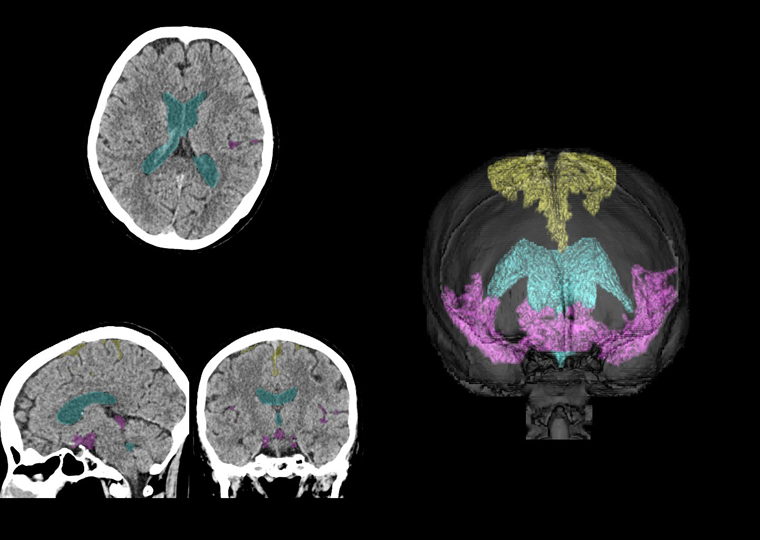

高位円蓋部・正中のくも膜下腔、脳室、シルビウス裂・脳底槽を領域ごとに検出することで、体積比の算出が可能となり、ハキム病の診断に重要なDESHの判定を支援する。

黄色:高位円蓋部・正中のくも膜下腔、水色:脳室、赤紫色:シルビウス裂・脳底槽